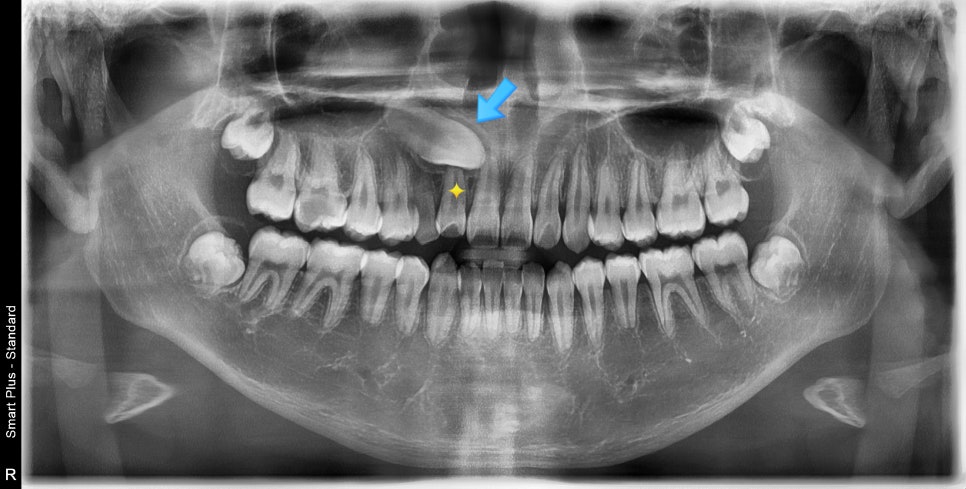

매복치의 위치가 항상 중요한 요소입니다.

이 친구가 매복송곳니를 뺀 이유 중 가장 큰 이유는 노란색으로 표시된 부분의 치아의 뿌리를 녹일 위치였기 때문입니다.

송곳니를 내리면 두번째치아가 손상을 입고

두번째를 빼자니 차라리 송곳니를 빼는게 심미적으로 유리하기 때문에

최종적으로 송곳니를 빼기로 한거죠.

추가적으로 돌출입도 있었기 때문에 모든 치아가 정상 맹출이 되어있더라도

4개의 치아를 빼는것이 유리한 아이었습니다.